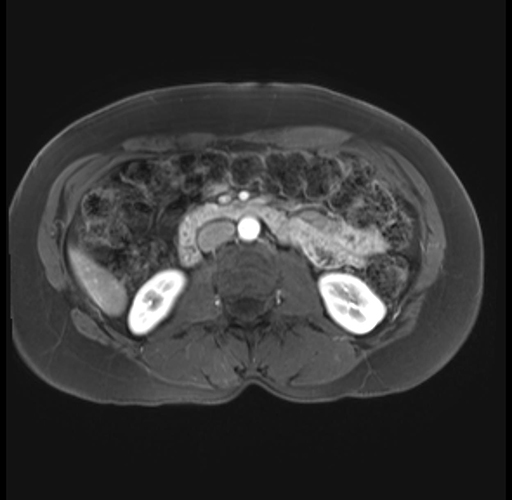

Imaging Analysis

Look through the patient's CT scan to identify any areas of concern for the necessary procedure.

Based on your CT findings, which issue(s) are present and would give reason for "planned slowing down moment(s)" in this case?